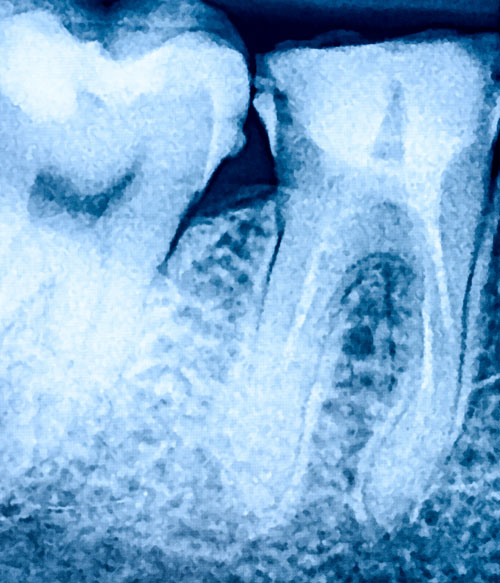

La parodontite (conosciuta comunemente anche come piorrea) è una malattia infiammatoria che colpisce le gengive e l’osso di supporto dei denti, causata da batteri presenti nella placca. Il primo sintomo è normalmente il sanguinamento delle gengive (spontaneo o causato dall’uso dello spazzolino) al quale può seguire un aumento della mobilità di uno o più denti o il cambiamento di posizione, fino ad arrivare alla perdita degli stessi.

Durante la prima visita eseguiamo la diagnosi attraverso il sondaggio parodontale, per esaminare lo stato di salute gengivale e osseo: così possiamo individuare da subito la presenza, il numero e la profondità delle zone colpite.